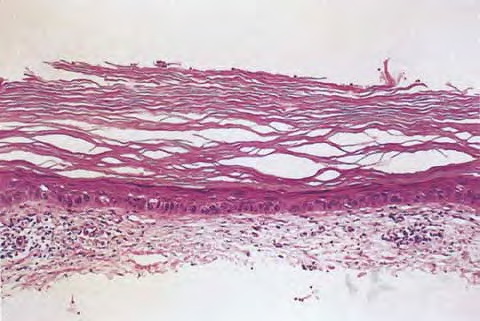

Arsenical keratoses = التقران الزرنيخي ARSENICAL KERATOSES Arsenical keratoses (ArKs) are precancerous lesions found in association with chronic arsenicism. These lesions have the potential to develop into invasive SCC. Arsenic is a ubiquitous element that has no color, taste, or odor. It has the potential to cause characteristic acute and chronic syndromes in persons exposed […]